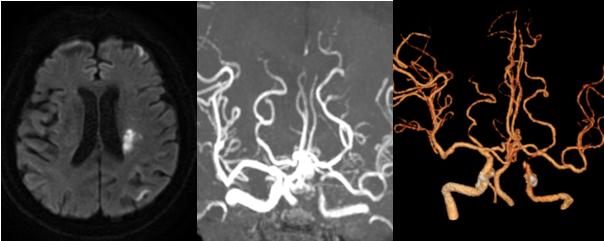

神经内科董万利主任带领团队对胡大爷的病情进行了分析评估。患者头颅磁共振发现左侧大脑中动脉供血区多发脑梗死,CTA+CTP检查提示:左侧颈内动脉颅内段混合斑块,管腔中-重度狭窄,最狭窄处接近闭塞;左侧大脑中动脉供血区缺血性灌注异常。诊断为:“脑梗死,左侧颈内动脉颅内段次全闭塞”。